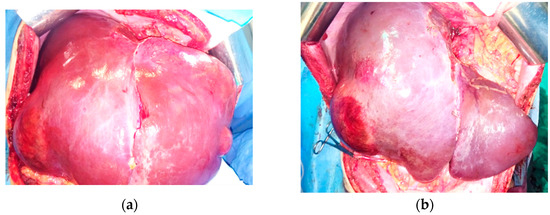

Figure 5.

First-stage surgery. Aspect of the liver: (a) prior to first-stage resection; (b,c) after resection; (d) resected specimen.